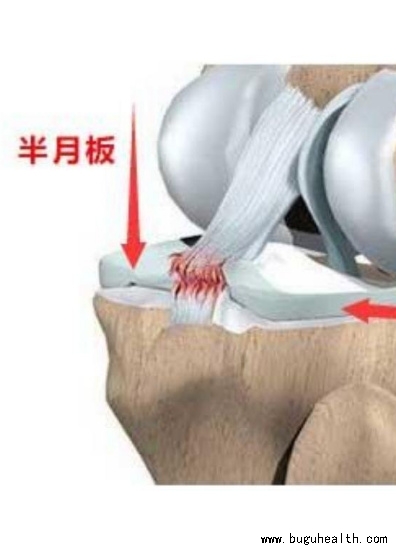

- ���°���ϥ�ؽ����ֹǺɹǼ�϶�ڵ���ά��״������֯����۳ʡ�C���ͣ��ʳ�Ϊ���°塣λ��ϥ�ؽ��ڲ�Ľ����ڲ���°壬���ơ�C���ͣ����Ľ��������°壬���ơ�O���͡������ڲ���°���ؽ����ܱ����ӽ��ܣ���Բ�����°��Ǵ����N������϶������Դ��°��ڹؽ��ڰ���ϥ�ؽ�һ���˶�����������.....

- ���°���ϥ�ؽ������һ��������֯�����֪����ϥ�ؽ������ŹɹǺ��ֹǣ����ǹɹ��¶�������Բ���ֹ��϶�������ƽ̨���������ֱ������Ļ����Ӵ����������㣬����������ѹǿ��ܴ����ǻ�ܿ챻ĥ�𣬲������ϵ��ȶ��Ի�ܲ�����εİ��°��������֮���ý�飬�ùɹǺ��ֹǵĽӴ����������ϱ�ý��ܶ��ȶ�����.....